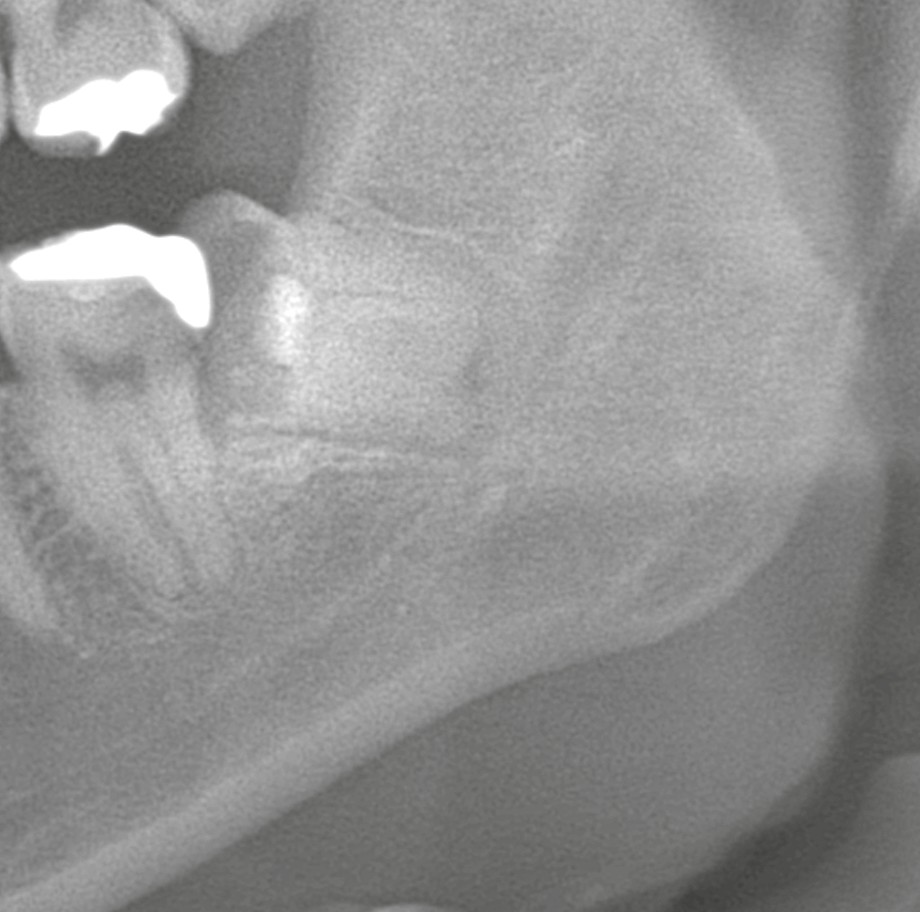

3ヶ月後のレントゲンでは、歯がわずかに移動し、下歯槽神経との距離が確保されたことを確認。そこで2回目の外科処置として、通常の埋伏抜歯を実施しました。

結果として、術後の麻痺やしびれは認められませんでした。